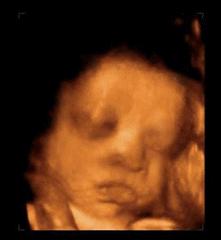

菌菌告诉你,小家伙不仅会做各种动作,表情更是丰富的不得了。

小脑袋一晃一晃的,我不答应,我不高兴,我要吃肉肉……

咦,妈妈在外面跟我说话,嘟嘴卖个萌先。

哈哈,妈妈肯定是被我萌到了,我都听到她的笑声了。

我还会吐舌头、扮鬼脸!

妈妈说我有当科学家的潜质哦!你认识这个人是谁吗?